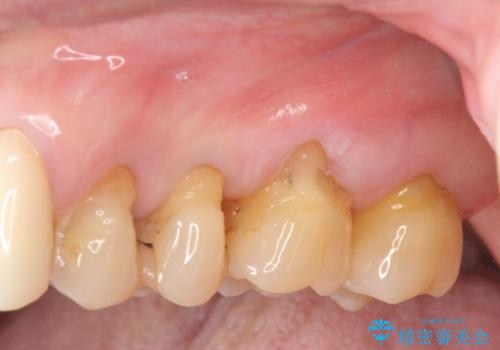

[ 上顎多数歯欠損 ] インプラント・義歯を用いた補綴

![[ 上顎多数歯欠損 ] インプラント・義歯を用いた補綴の症例 治療後](https://seimitsushinbi.jp/wp/wp-content/uploads/2020/09/8be5dd778f94eb578b5490a0ba817f10-1-500x350.jpg?v=1600566164)